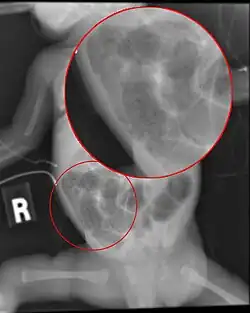

Radiograph of a baby with necrotizing enterocolitis

Diagnosis is usually suspected clinically, but often requires the aid of diagnostic imaging, most commonly radiography, which can show the intestines and may show areas with dead tissue or a bowel perforation.[18] Specific radiographic signs of NEC are associated with specific Bell's stages of the disease:[19]

Ultrasonography has proven to be useful, as it may detect signs and complications of NEC before they are evident on radiographs, specifically in cases that involve a paucity of bowel gas, a gasless abdomen, or a sentinel loop.[21] Diagnosis is ultimately made in 5–10% of very-low-birth-weight infants (<1,500g).[22]